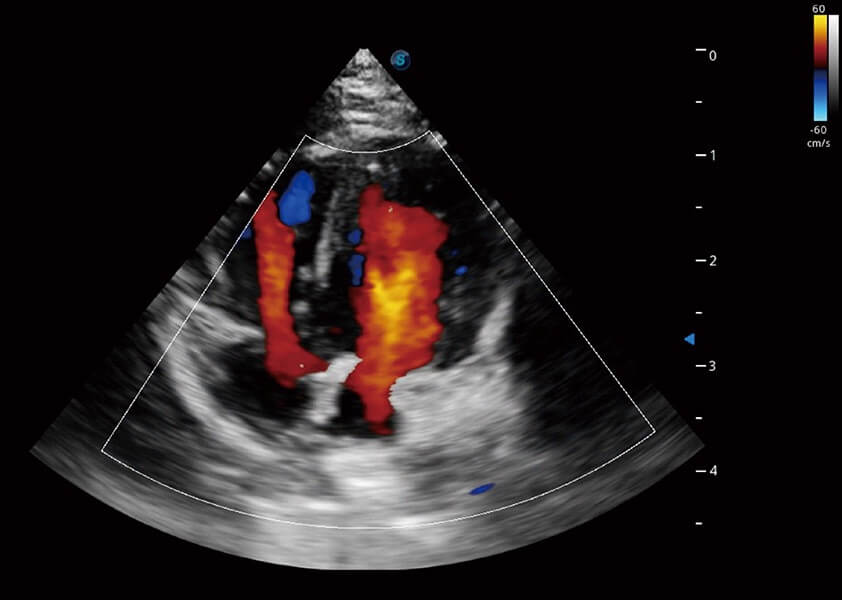

心脏解决方案

ProPet 60 配备了丰富的心脏探头群、先进的成像技术和专业的心脏测量工具,可帮助动物医生为不同体型和生理结构的动物提供心脏和心肌功能的全面评估。

• TDI 组织多普勒成像

实时用颜色表示心肌组织运动,观察和定量组织的运动情况,对快速检测与评估心肌的灌注和活性、电传导及心肌收缩和舒张功能等均能提供重要的诊断信息。

• MQA 心肌定量分析

通过心肌识别技术与二维斑点追踪技术相结合,对心脏的超声图像进行量化分析。计算心肌17个节段的应变、应变率、速度、位移等,并通过牛眼图的形式进行呈现。

• AMM 解剖M型

通过360度任意调节3条M型取样线,在同一心动周期上观察心脏不同位置的运动曲线,得到准确的心功能测量数据,有效评估心肌运动及左心室功能。

• Stress Echo 负荷超声心动图

具备多种协议可选,同时支持17阶段划分法和专业的SE报告。

优异的基础图像

(犬)四腔心血流